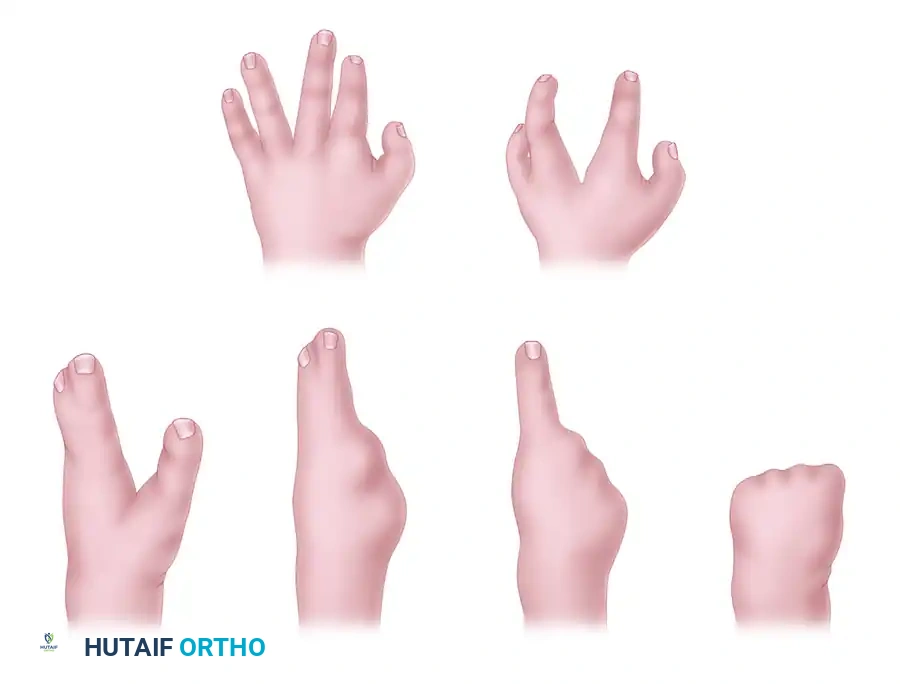

Central longitudinal deficiencies of the hand, historically termed "cleft hand" or "ectrodactyly," represent a complex spectrum of congenital anomalies characterized by the suppression or absence of the central rays (typically the long finger and third metacarpal). These deformities present significant functional and aesthetic challenges, requiring a nuanced, highly individualized surgical approach.

Maisels’ suppression theory illustrates that milder deformities present as a simple cleft without significant tissue loss. As the severity of suppression increases, the absence of the central ray is noted first, followed by the progressive loss of the radial rays, and eventually the loss of all rays.

1. The Typical Pattern (True Cleft Hand)

Present at birth, this pattern features a central V-shaped defect in the palm. The long finger is usually entirely absent. The remaining digits bordering the cleft (index and ring fingers) frequently exhibit varying degrees of syndactyly and a deficient, narrowed first web space. The deformity is often bilateral and inherited in an autosomal dominant pattern with variable penetrance. Foot deformities (cleft foot) are frequently associated.

2. The Atypical Pattern (Symbrachydactyly Variant)

In the atypical pattern, the hand typically presents with only two digits: one on the radial border (thumb) and one on the ulnar border (small finger). A shallow U-shaped defect intervenes along the distal palm. The deformity is usually unilateral, sporadic, and lacks associated foot anomalies. In severe forms, all digits except the small finger may be absent.

Flatt’s classification of central deficiencies: Group 0, all bones present; Group 1, one ray involved; Group 2, two rays involved; and Group 3, three rays involved.

Children with central hand deficiencies often develop remarkable compensatory dexterity. However, the psychological impact of the "clawlike" appearance becomes pronounced as the child enters grade school.